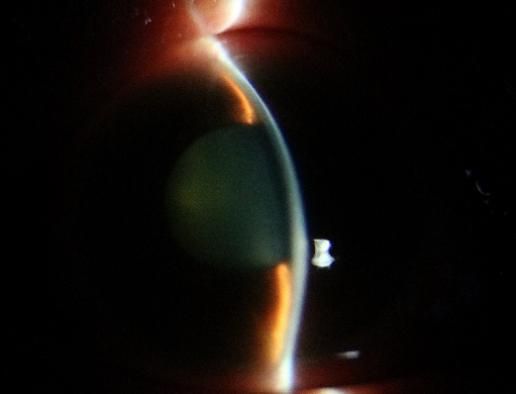

安徽省蚌埠市60岁的张阿姨在前往兰州的火车上突发右眼胀痛、视物模糊,还伴有头晕、恶心、呕吐等症状。休息后这些症状并未缓解,张阿姨在西安站下车后立即被送至我院急诊科就诊。急诊科医生考虑到症状可能与眼部疾病有关,遂请眼科医生会诊。经眼科医生仔细检查后发现,张阿姨右眼视力仅为指数,眼压高达75mmHg(正常眼压范围为10-21mmHg),角膜上皮弥漫性雾状水肿,前房极浅,瞳孔欠圆,直径约6mm,晶状体混浊。诊断为张阿姨是原发性急性闭角型青光眼,即右眼急性发作期、左眼临床前期,双眼老年性白内障。张阿姨随即被收住眼科病区,接受局部及全身降眼压药物治疗,效果不佳。考虑到持续高眼压对视神经的损伤,眼科范雅稚副主任当机立断为患者进行前房穿刺放液,眼压暂时得到有效控制。但经过一周的治疗及观察后,她的角膜始终未恢复透明,角膜内皮皱褶严重。

患者前房穿刺放房水并使用缩瞳药物后

随后进一步的辅助检查发现张阿姨的眼部情况极为复杂,双眼小眼球的结构使得眼部的房水循环存在一定障碍,右眼前房深度仅1.27mm,左眼前房深度1.67mm,前房极浅的状况进一步阻碍了房水的正常流通,是引发眼压升高的重要因素之一。同时,张阿姨右眼还存在睫状体脱离的问题,这不仅影响了眼部的正常生理功能,还增加了治疗的难度。她的中央角膜处于灰白水肿状态,角膜不透明这一情况使得内路微创手术及白内障手术无法实施,医生难以清晰观察眼内结构,手术风险会大幅增加。如果不立刻手术,等待角膜恢复透明的过程中,患者又随时可能出现二次青光眼大发作的情况。

UBM结果提示:右眼前房极浅,部分房角关闭,睫状体浅脱离